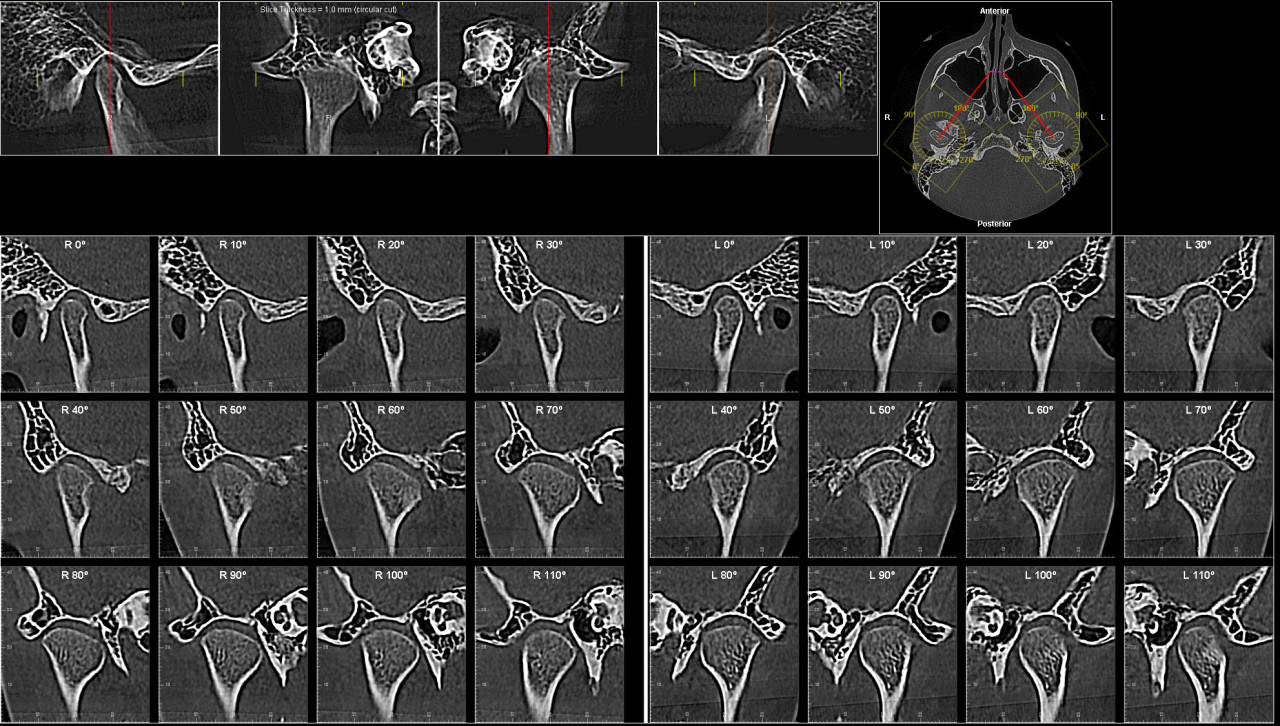

Вот есть еще такие снимки

По этим снимкам также видно выраженную скученность зубов и анатомически узкие зубные дуги. Нижняя пятёрка лежит неправильно, а верхним зубам явно не хватает места. Это подтверждает, что вариант с удалением части премоляров более предсказуем и стабильный для получения симметрии и правильного прикуса.

Здравствуйте. По вашим КТ видно выраженную скученность, узкую верхнюю дугу и проблему с нижней пятёркой, один зачаток расположен горизонтально, второй отсутствует. При такой анатомии ортодонтическое лечение без удаления зубов часто приводит к нестабильному результату или чрезмерному расширению, которое челюсть просто не удержит.

По снимкам можно сказать следующее:

- верхние резцы действительно выдвинуты вперёд, места мало

- симметрия зубных рядов нарушена из-за отсутствия одной нижней пятёрки

- восьмёрки по расположению не выполнят функцию премоляров

-вытяжение горизонтально лежащего зачатка пятёрки технически возможно, но долго, сложно и не всегда удачно

-при сохранении всех зубов есть риск рецидива и ухудшения профиля лица

Поэтому вариант с удалением верхних пятёрок и проблемной нижней пятёрки выглядит более предсказуемым с точки зрения симметрии и стабильности результата. Это не значит, что другой план неверен, но он более рискованный и требует очень опытного врача и долгого лечения.

Большое спасибо за Ваше мнение! Есть еще такие снимки

По этим снимкам видно, что суставы и положение нижней челюсти также не дают достаточного пространства для безопасного расширения дуг. При такой анатомии лечение без удаления зубов может привести к перегрузке сустава и рецидиву. Поэтому удаление отдельных премоляров и проблемной нижней пятёрки остаётся более надёжным вариантом для стабильного результата.